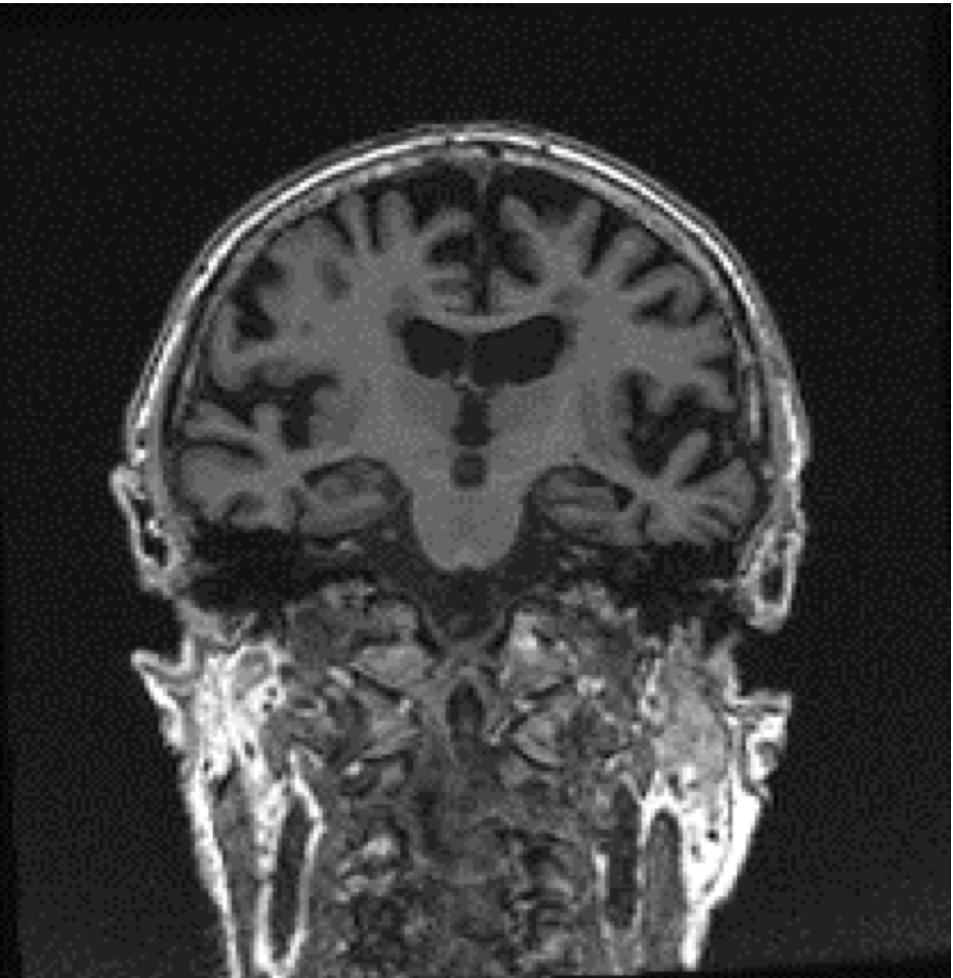

Approximately half of all patients who experience stroke, brain bleeds, or blocked blood vessels, identified on MRI or head CT in this study, had high blood pressure or type 2 diabetes.